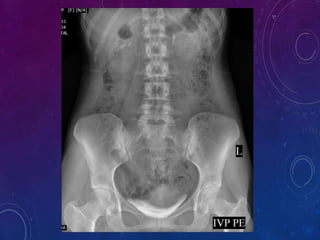

 Plain X-Ray KUB/Scout film -14x17

Plain X-ray KUB /Scout film provides valuable information and sometimes

indicates provable diagnosis.

Useful in assessing :

1) Calculus

2) Intestinal abnormalities

3) Intestinal gas pattern

4) Calcification

5) Abdominal mass

6) Foreign body